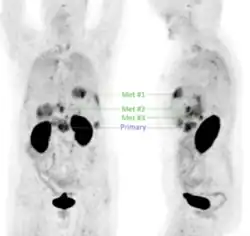

Neuere Forschungen setzen sich intensiv mit der Anwendung der Positronen-Emissions-Tomographie (PET) für die Bildgebung des (duktalen) Pankreaskarzinoms (PDAC) auseinander, wobei das Interesse insbesondere auf die Detektion von Metastasen fokussiert ist. Für PET ist die intravenöse Gabe eines Radiotracers erforderlich, also eines Radiopharmakons, welches mit einem Positronen emittierenden Radionuklid markiert ist. Der für die PET am häufigsten eingesetzte Tracer, 18F-Fluordesoxyglucose (FDG) ist jedoch für die Diagnostik des PDAC nur bedingt geeignet, da dessen vergleichsweise langsames Wachstum und die desmoplastische Gewebsstruktur oft dazu führt, dass FDG zu gering angereichert wird, um eine verlässliche PET-Diagnostik zu gewährleisten.[43] Die Tumorzellen von PDAC weisen jedoch in den meisten Fällen (>88 %) eine Überexpression des Oberflächenproteins αvβ6-Integrin auf, weshalb Radiopharmaka, die spezifisch an dieses Protein binden, für die PET-Bildgebung von PDAC genutzt werden können.[44] Im Zuge der experimentellen klinischen Anwendung verschiedener αvβ6-Integrin-gerichteter Radiotracer zeigte sich, dass 68Ga-Trivehexin[45] gut für die PET-Bildgebung des metastatischen PDAC geeignet sein könnte (siehe Beispielbild), insbesondere aufgrund der vergleichsweise geringen unspezifischen Anreicherung im gastrointestinalen Bereich.[46] Infolgedessen wurde 68Ga-Trivehexin experimentell für die PET-Bildgebung in einigen PDAC-Fällen[47][48][49] sowie einer größeren Kohorte (44 Patienten)[50] mit PDAC oder Verdacht auf PDAC erfolgreich diagnostisch angewendet.